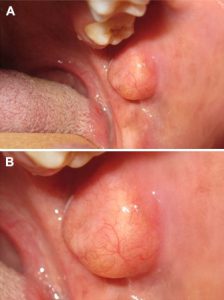

بیشتر موارد لیپوم پس از دهه ششم زندگی یا در افراد مسن گزارش می شوند و میانگین سنی بروز آن ۶۰ سال است. لیپوم های حفره دهان در کودکان نادر هستند. بر اساس گزارش ها، لیپوم های دهانی معمولاً در مکان های آناتومیک مختلف، مانند غدد بزاقی اصلی، روی بافت های نرم مانند مخاط گونه، لب ها، زبان، گونه ها، کام (سقف دهان) و کف دهان رخ می دهند و هیچ دردی ندارند. ممکن است مانند یک توده چربی یا یک توپ احساس شود. مکان های داخل دهانی که معمولاً گزارش می شوند، ضایعات روی مخاط گونه یا دهلیز گونه هستند. بیمارانی که از این لیپوم های دهانی غیرمعمول رنج می برند، ممکن است ماه ها یا حتی سال ها ضایعات بدون علامت بدون درد یا با رشد آهسته داشته باشند. معمولاً هیچ علامت دیگری مانند خونریزی یا مشکل در بلع ایجاد نمی کند.

لیپوم ها معمولاً بدون علامت هستند، اما در نهایت با بزرگتر شدن، ممکن است در گفتار و جویدن اختلال ایجاد کنند. در این صورت بیمار از تداخل ضایعه شکایت می کند. با این حال، در معاینه بالینی، این ضایعات زرد رنگ با قوام نرم و خمیری به نظر می رسند. آنها همچنین به خوبی مشخص هستند و ضایعات ممکن است در برخی موارد موج دار و گره دار باشند.